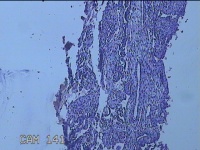

宫腔内容物

性别

女

年龄

47岁

临床诊断

1.异常子宫出血 2.慢性宫颈炎

一般病史

不规则阴道流血21天。

标本名称

大体所见

灰白暗红色不规则碎组织2.5x1.8x0.3cm一堆。

图4